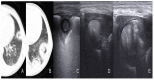

Results: We included 17 studies, reporting a total of 274 patients with M. pneumoniae, 30 with fungal infection and 213 with pulmonary tuberculosis (TB). Most of the studies on M. pneumoniae in children found a specific LUS pattern, mainly consolidated areas associated with diffuse B lines. The typical LUS pattern in TB consisted of consolidation and small subpleural nodes. Only one study on fungal disease reported LUS specific patterns (e.g., indicating "halo sign" or "reverse halo sign").